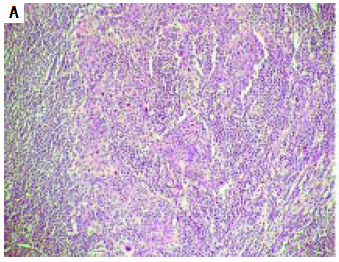

A 73-year-old Asian female with chronic hepatitis B presented with periportal lymphadenopathy, 5 years after she underwent partial hepatectomy for hepatocellular carcinoma (HCC). Segment 7 liver resection specimen at the initial presentation revealed a cirrhotic liver with a 1.2 cm poorly-differentiated HCC accompanied by dense lymphocytic inflammatory infiltrate (Figure 1A) and microvascular invasion (stage pT2 based on American Joint Committee on Cancer, 7th edition). The tumor-infiltrating lymphocytes predominantly comprised of T-lymphocytes (Figures 1B-1C) and the resection margin of the hepatectomy specimen was negative for tumor involvement. During the most recent follow-up, computed tomography scan revealed a 3.4 cm mildly arterial enhancing nodule in porta hepatic with washout on venous phase, concerning for a recurrent HCC in the caudate lobe. Enlarged peripancreatic lymph node (1.6 cm) and precaval lymph node (1.1 cm) were also identified. Her serum alpha-fetoprotein level at the time was within normal limits, 2.4 ng/mL (reference range: 0.0-9.0 ng/mL). The patient subsequently underwent surgical resection for diagnostic and therapeutic purposes. At the time of surgery, no caudate lobe lesion was identified and the porta hepatic nodule was found to be an enlarged porta hepatic lymph node.

Figure 1A The primary hepatic tumor shows a poorly differentiated carcinoma with abundant tumor-infiltrating lymphocytes (hematoxylin-eosin, 100x).